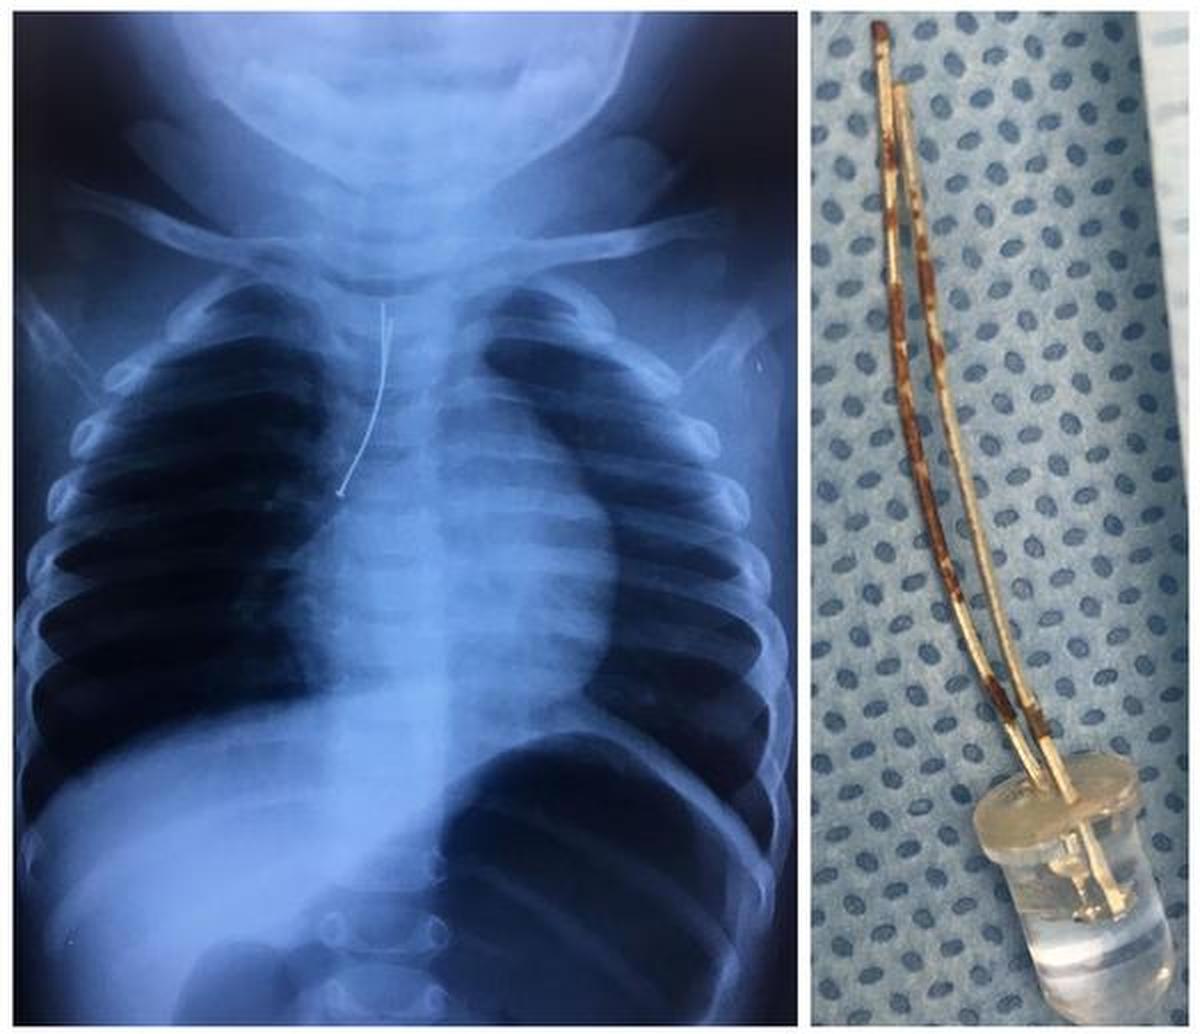

The supine chest view of the neonatal patient is a common radiographic examination when examining preterm patients 1. X-ray exams are used to help diagnose a wide variety of injuries and illnesses in children. Baby chest x ray tubechest trochar cannula appropriate for baby 3 way tap 10 ml syringe skin disinfectant.

In most cases an anteroposterior view of the chest would provide sufficient diagnostic information. Lateral chest and abdomen views should be included. Although not overall technically demanding the.